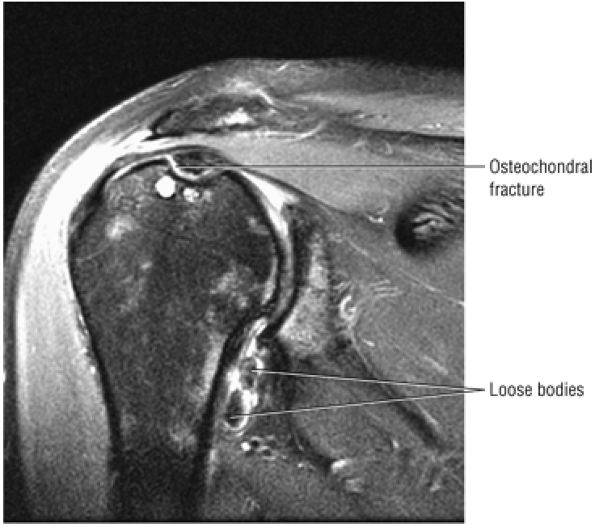

FIGURE 8.102 ● (A) The anterior undersurface of the acromion and the coracoacromial ligament form the coracoacromial arch. The subacromial subdeltoid bursa facilitates the passage of the rotator cuff and proximal humerus under the coracoacromial arch. (B) A superior axial image shows the anterior-to-posterior extent of the coracoacromial (CA) ligament perpendicular to the supraspinatus tendon. The fluid in the subacromial-subdeltoid bursa represents fluid between two serosal surfaces in contact with each other. One serosal surface is contributed by the undersurface of the coracoacromial arch and deltoid, and the other serosal surface is on the bursal side of the cuff.

|

![]() |

FIGURE 8.103 ● Pseudospur. The normal broad attachment of the coracoacromial ligament to the inferior surface of the acromion is shown on (A) T1-weighted coronal oblique and (B) sagittal oblique images. The low-signal-intensity acromial cortex (black arrows) and adjacent coracoacromial ligament and lateral slip of the deltoid attachment (white arrows) give the false impression of a small subacromial spur in the coronal plane. This pseudospur should not be misinterpreted as impingement; otherwise, unnecessary acromioplasties may be performed on patients with a normal coracoacromial ligament attachment and no associated acromial spurs.